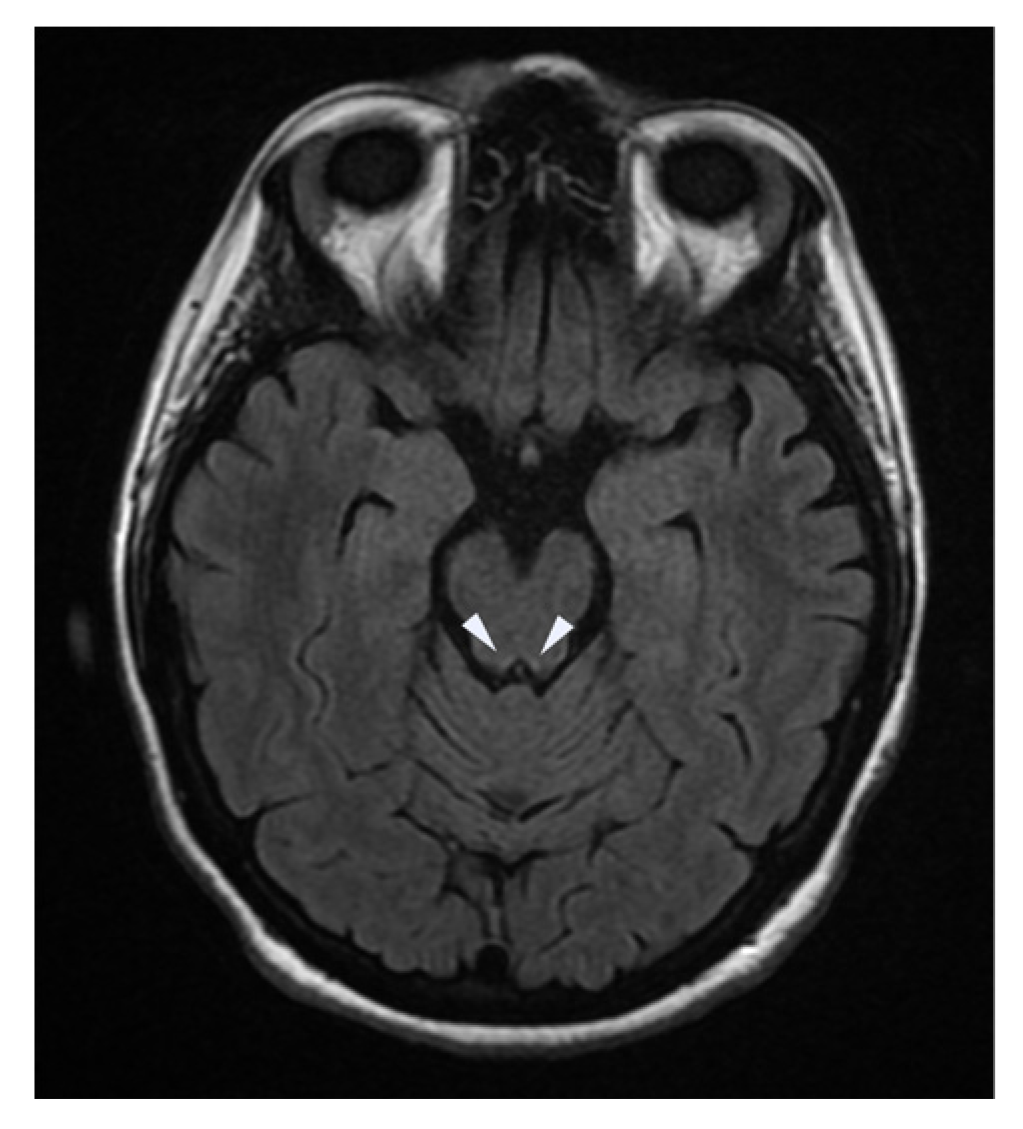

| Brain Imaging | MRI of the brain and spinal cord showed hyperintensity of:

|